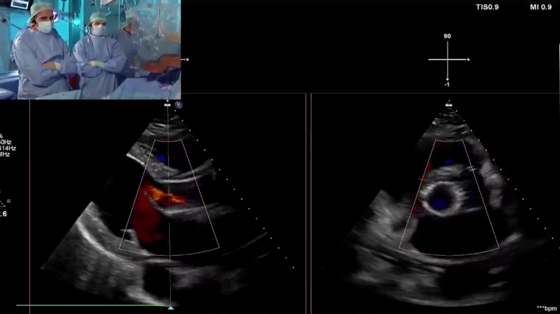

来自德国University Hospital Mainz的Hendrik Treede教授Alexander Tamm教授带来的一例症状性主动脉瓣反流患者的TAVI手术直播,患者为65岁男性,因呼吸困难就诊,纽约心功能分级III级,近期因前降支重度狭窄行PCI,同时合并肾功能受损及高血压。TTE/TEE超声结果显示为右窦脱垂导致的重度主动脉瓣反流,左室扩张,左室射血分数轻度降低。Hendrik Treede教授详尽地讲解了Trilogy系统的步骤操作,并完整展示了器械植入的全流程,手术取得了极佳的结果,良好的血流动力学,术毕造影及超声结果显示无主动脉瓣反流,无瓣周漏。术后讨论中,Hendrik Treede教授与Alexander Tamm教授再次肯定了整个系统的精巧设计,Trilogy独有的定位键可实现与原生瓣叶对齐,同时为瓣叶无钙化的单纯反流病例提供锚定。其瓣膜流出端超大网孔设计和瓣叶定位技术也为冠脉再介入带来优势。随着器械应用和经验的积累,瓣膜选择策略更加适配患者情况,改善因瓣膜选择过大和植入过深导致的传导阻滞。